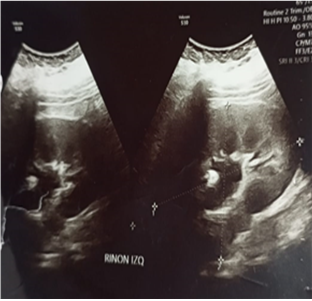

Se realiza ecografía ginecológica compatible con hematómetra (Vol. 291. 44), ecografía abdominal se aprecia dos masas sólidas, en zona de excavación pelviana, una mide (7,6 x 5,8 x 5,6 cm) y otra (8,7 x 5,9 x 5,5 cm), ambas se unen en una brida, no se observa imagen endometrial, riñón derecho ausente, riñón izquierdo mide 11,2 x 8,2 cm., se observa leve dilatación pielocalicial. (figura 1A- 1B).

Figura 1. A: ecografía ginecológica, evidencia imagen econegaticas compatible con hematómetra, dos masas sólidas, ambas se unen por una brida, miometrio homogéneo, útero en anteroversoflexión, útero didelfo, saco de Douglas libre |

Figura 1. B: ecografía abdominal, que evidencia presencia de riñón izquierdo y dilatación de los calices menores en forma moderada, agenesia renal derecha |